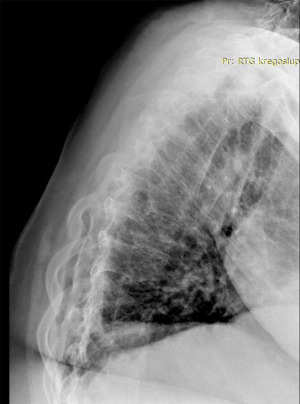

Radiographs obtained in 2023 (Figures 1,2) demonstrated progression of spine deformity with Cobb angle measurements of 60° in the thoracic region and 54° in the thoraco-lumbar spine with vertebral rotation. Computed tomography (CT) and magnetic resonance imaging (MRI) studies revealed fusion of the posterior elements of the vertebrae in Th5-L3, degenerative changes in Th12-L5 with herniated discs L3/L4, L5/S1. Secondary to the scoliosis, the spinal cord was pressed to the right wall of the spinal canal in section Th12-L3 and stenosis of the left intervertebral foramen with compression of the left intervertebral nerves at the level of L3/L4, L4/L5, L5/S1, which accounted for the patient’s neurological symptoms. The patient was diagnosed with type 2 adult scoliosis.